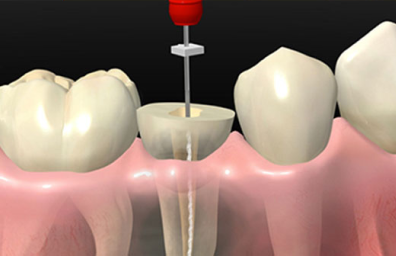

La endodoncia es una especialidad de la Odontología que permite conservar en boca los dientes dañados y que se conoce habitualmente como “tratamiento de conductos”. Este tratamiento consiste en realizar una completa evaluación diagnóstica clínica y radiográfica del diente afectado y posteriormente con diferentes procedimientos bajo anestesia local se trata la pulpa dental, el órgano interno del diente que está dañado, evitando así la extracción de éste. En nuestra clínica de endodoncia la primera prioridad es aliviar el dolor, eliminar las infecciones dentales y solucionar de la mejor forma para cada paciente su afección dental. Los procedimientos endodónticos se realizan bajo magnificación, instrumentación mecanizada y técnicas de vanguardia.